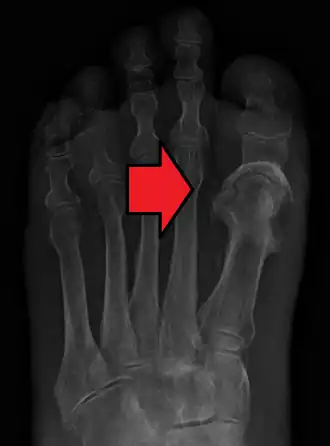

| Osteomielite no hálux | |